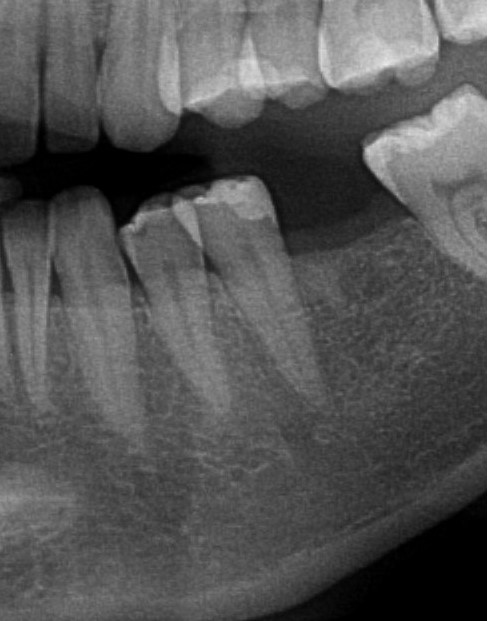

Pan Antonii z Katowic zgłosił się z prośbą o metamorfozę uśmiechu w trakcie diagnostyki w dentestica Katowice okazało się, że jednym z problemów Pana Antoniego jest zatrzymana dolna trójka. Po niezbędnej diagnostyce usunięto z kości zatrzymany ząb i jednocześnie zregenerowano ubytek kostny po zębie pozyskanym ze zmielenia tego zęba biomateriałem (w specjalnej procedurze, młynek – Liberdent), wspomagając gojenie pozyskaną z krwi Pacjenta autogenną fibryną bogatopłytkową (PRF), dzięki takiemu postępowaniu utworzono stabilne podłoże pod przyszły implant, a używając materiałów autogennych zminimalizowano ryzyko. Kolejnym etapem było posadowienie implantu, obecnie Pacjent oczekuje na wykonanie korony na implancie.

Do tego czasu Pacjent jest zaopatrzony mostem tymczasowym żeby zamaskować brak dolnej trójki.